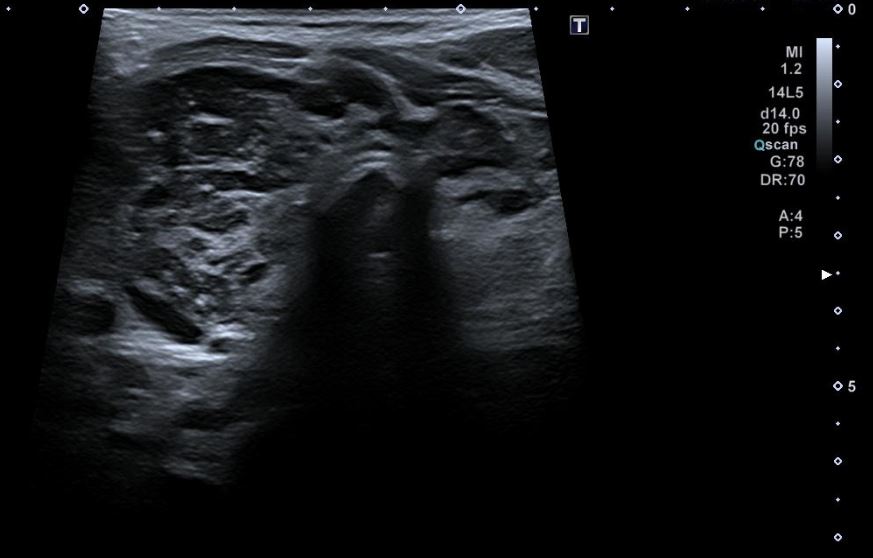

Una vez realizada la anamnesis y la exploración física, se decide realizar una ecografía clínica en la consulta, donde se objetiva un aumento difuso de tamaño del lóbulo tiroideo derecho (33,9 x 38,7 mm), levemente hipoecogénico, con áreas anecoicas en su interior y adenopatías asociadas. Se aplica Doppler color resultando positivo.

El juicio clínico es de una tiroiditis aguda, por lo que se deriva al paciente a urgencias hospitalarias. En urgencias se solicita una analítica sanguínea en la que destaca Leucocitos 7,34 x 103 y PCR 68 mg/L; y una ecografía reglada donde se informa de «tiroides aumentado de tamaño a expensas de lóbulo tiroideo derecho con alteración de la ecogenicidad del parénquima que sugiere proceso infiltrativo afectado al lóbulo derecho, istmo y región anterior del lóbulo izquierdo, no pudiendo apreciar etiología infiltrativa o tumoral».